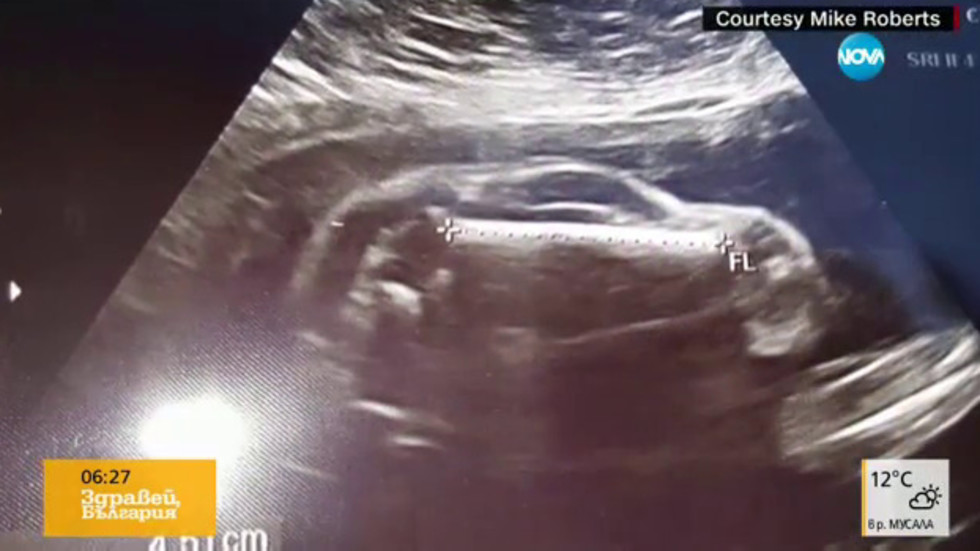

Резултатите от ултразвук предизвикват десетки шеги в САЩ

Млада жена в САЩ е "бременна с автомобил". Тази шега започнал бащата на бебето, след като съпругата му отишла на преглед с ултразвук.

Полученият образ напомня силуета на автомобил. Бащата качил снимка в интернет. И започнали предположения какъв модел е автомобилът.

Някои виждат спортни коли. Други - миниванове. А докторите казали на съпругата на шегаджията, че едно е сигурно - колата е момче и се развива нормално.